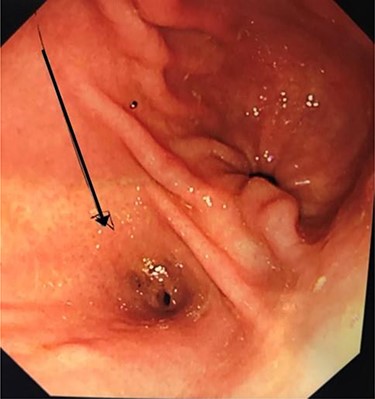

Computerized tomography demonstrated an enhancing soft tissue thickening in the gastric pylorus with soft tissue extension into the left lobe of the liver, invasion of the left intrahepatic bile ducts with obstruction and dilatation of the left sided intra- and extrahepatic biliary tract (Fig. 1). Oesophagogastroduodenoscopy (OGD) showed a pre-pyloric fistula (Fig. 2).

Oesophagogastroduodenoscopy (OGD): pre-pyloric fistula—ectopic opening of the ACBD.